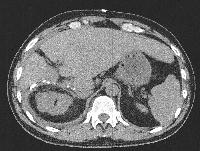

Πρόκειται για άνδρα ασθενή 50 ετών που υποβλήθηκε σε υπέρηχο άνω κοιλίας στα πλαίσια προληπτικού ελέγχου, ο οποίος ανέδειξε ογκόμορφη εξεργασία του ήπατος. Ακολούθησε αξονική τομογραφία, κατά την οποία διαπιστώθηκε μάζα μεγέθους 7 εκατοστών στα ηπατικά τμήματα 4a, 5 και 8 (εικόνα 1) που διηθούσε τη δεξιά και τη μέση ηπατική φλέβα. Επιπλέον, ανιχνεύθηκαν υψηλά επίπεδα α-Fp. Τέθηκε η διάγνωση του ηπατοκυτταρικού καρκινώματος σε έδαφος φυσιολογικού ηπατικού παρεγχύματος. Η ογκομέτρηση των τμημάτων 1, 2 και 3 ανέδειξε προβλεπόμενο σχετικό όγκο ηπατικού υπολείμματος 13,5%. Ο ασθενής υποβλήθηκε σε δεξιό πυλαίο εμβολισμό (εικόνα 2). Τέσσερεις εβδομάδες αργότερα, υποβλήθηκε σε ανάλυση MEVIS, σύμφωνα με την οποία αποφασίστηκε η διενέργεια δεξιάς εκτεταμένης (parenchymal sparing, anterior approach) ηπατεκτομής με προβλεπόμενο σχετικό όγκο ηπατικού υπολείμματος 37,2%. Πέντε εβδομάδες μετά τον πυλαίο εμβολισμό, ο ασθενής υποβλήθηκε στην προαναφερόμενη ηπατεκτομή (εικόνες 4, 5). Έλαβε εξιτήριο την 7η μετεγχειρητική ημέρα. Στην εικόνα 6 παρουσιάζεται το αναγεννώμενο ηπατικό υπόλειμμα, 15 ημέρες μετά την επέμβαση.